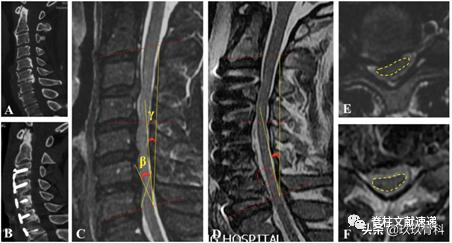

下图所示为骨化块残留情况。

下图所示为骨化块宽度评估,图B为宽基底骨化块,易残留。

术前应仔细阅片,明确骨化块与椎弓根的关系,B、E易切开,D、G易残留。

另一个骨化块残留的因素是斜行截骨槽。如下图所示,佩戴头戴式放大镜易导致截骨槽倾斜,同侧出现骨化块残留。

做完截骨槽时,可能会遇到下图两种情况,应用神经钩探查以明确截骨槽宽度是否足够。也可用术中CT进行确认。

文章认为宽基底OPLL采用ACAF出现骨化块残留率为71.4%,会导致神经功能恢复不良,术前应仔细阅片充分评估,另外,斜行截骨槽易导致骨化块残留。